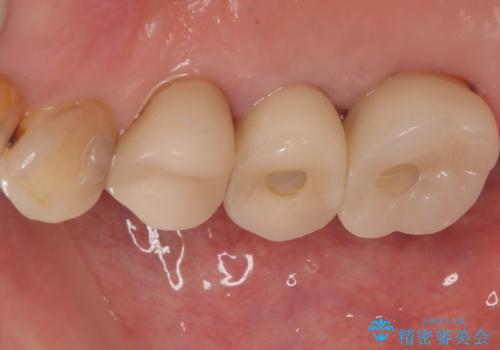

破折して抜歯となった奥歯 抜歯即時埋入・即時荷重インプラントによる補綴治療

- 奥歯の歯茎が腫れているとのことで来院された患者様です。

奥歯の歯根が破折している可能性が高く、破折している場合には抜歯となるため、本当に破折しているのか確認をしてほしいとのことでした。

歯肉を開いて確認をしたところ、著しく骨欠損しており、目視でも歯根破折が確認されました。

3つある歯根の内、1つのみに骨欠損がある状態で、インプラント埋入に十分な骨の状態でした。

抜歯即時埋入・即時荷重の適応と判断されたため、インプラントによる補綴治療を行うこととしました。

埋入時に十分な安定値が獲得でき、埋入した際に仮歯を装着することができました。

術後の経過は安定しており、抜歯から3ヶ月で治療を終えることができました。